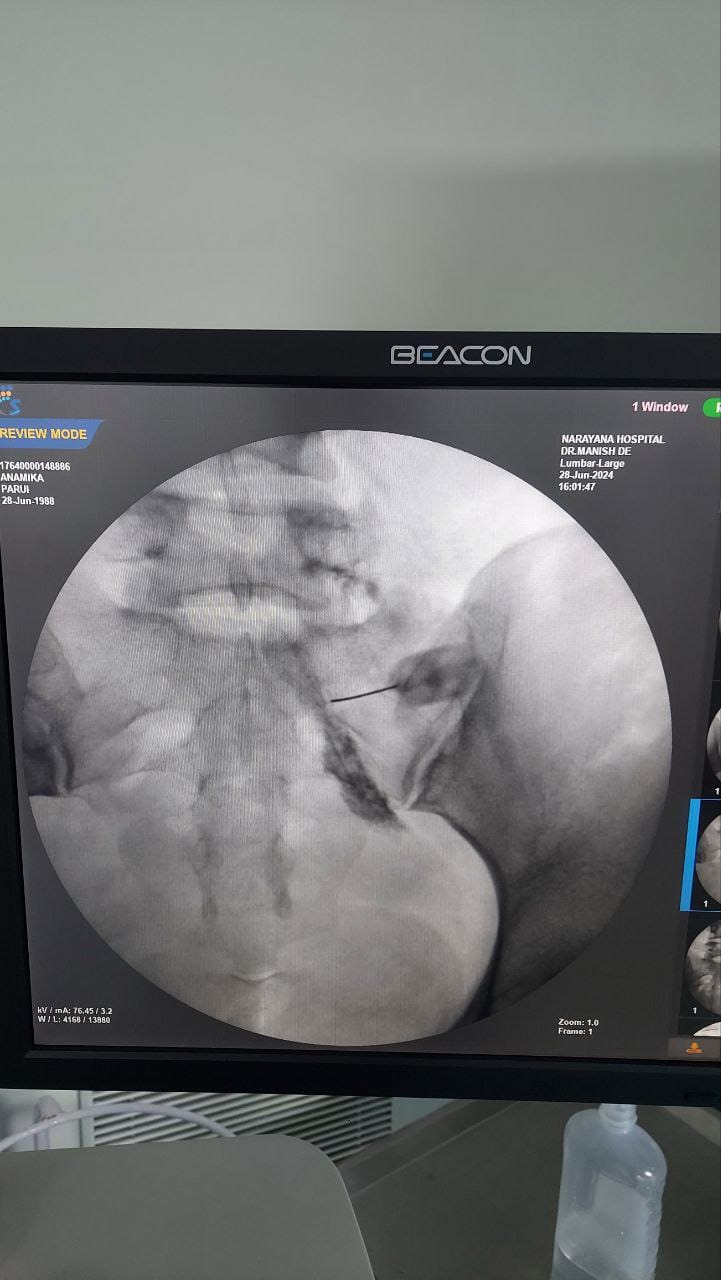

Struggling with chronic pain? Get advanced, personalised pain management from Dr. Manish De, one of Kolkata’s leading pain specialists. From knee pain, heel pain, low back pain, frozen shoulder, migraines, cancer pain to post-TKR persistent pain—Dr. De offers safe, evidence-based treatments across multiple locations: